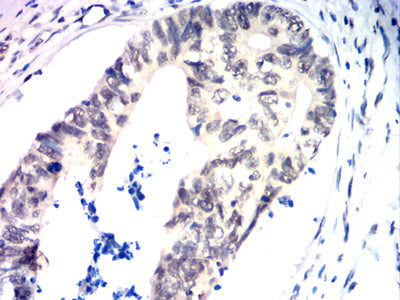

Immunohistochemical analysis of paraffin-embedded human liver cancer tissues using TDP43 mouse mAb with DAB staining.